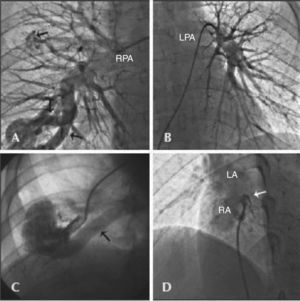

The patient was then submitted to angiography through the right femoral artery and vein, which showed no coronary lesions, preserved left ventricular function, and presence of pulmonary arteriovenous malformations of high flow at the base (large fistulous sac with two adductor arteries, with diameters of 8mm and 10mm) and middle third of the right lung (small fistula with an adductor artery of 3.5mm in diameter), and patent foramen ovale (Figure 1). There was no hypertension in left and right chambers, arterial saturation was low (84.2%), and the calculated flow through the fistula was 0.89L/min, with a flow ratio Qp/Qs of 0.83.

– In A, selective injection into the right pulmonary artery showing the presence of arteriovenous malformations, one of which was simple (arrow, upper portion) and another complex, with two adductor arteries (arrows, lower portion). In A, selective injection into the left pulmonary artery showing absence of fistulae. In C, selective injection into the adductor artery showing fistulous sac and involved vein (arrow). In D, injection into the patent foramen ovale in left cranial anterior oblique view showing passage of contrast from the right atrium to the left atrium (arrow). RPA, right pulmonary artery; LPA, left pulmonary artery; LA, left atrium; RA, right atrium.